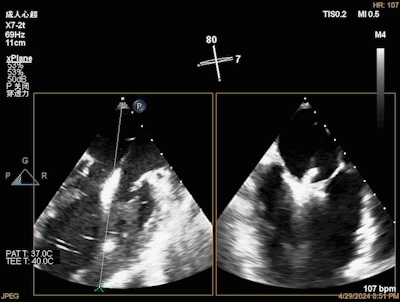

团队在反流最严重的2区精准植入1枚二尖瓣夹,即刻反流下降至微量,血压即刻上升20mmHg,跨瓣压差不升反降,由3mmHg降至2mmHg,改善效果明显,手术仅耗时一个半小时。 这是时隔四年继2020年指导开展区域内首例TAVR(经导管主动脉瓣置换)手术之后,陈茂教授再次带领华西团队,指导开展内自同城区域首例TEER术。陈茂教授对四院心内科心超图像的采集、房间隔穿刺的技巧、手术流程细节的把握、团队的默契配合、术前术后的管理表示称赞,鼓励四院心内科再接再厉造福区域患者。 患者为71岁老年女性,反复出现心累、气促已经超过10年,10多年来心衰的症状逐渐加重,间隔时间越来越短,且近1个月来已经3次因心衰住院,本次住院前已经无法耐受缓慢步行、如厕等日常生活,BNP超过了3000ng/ml。心电图为房颤,心超示左心室明显增大(65mm),重度二尖瓣反流(4+,CarpentierI+IIIb型),射血分数仅为31%。前叶长度:2.27cm且瓣尖增厚,后叶长度:1.14cm且局部钙化,瓣口面积:4.08cm2,反流宽度:1.7cm。患者及家属均拒绝外科开胸手术。 难点: 1.食道超声下该患者房间隔较厚较韧,且粗测高度仅为4.0cm,对穿刺的位置和技巧有较高要求; 2.左心扩大,反流宽度约17mm,放一个夹子可能不能有效解决反流,如放两个夹子需side by side 平行放置,但放置两个夹子有术后狭窄的风险; 3.前后叶对合似有间隙,若选用长宽夹子,会增加瓣叶张力,有瓣叶撕裂的风险,若选用短宽夹子,其捕获瓣叶的难度将增加; 4.患者心功能极差,手术需稳、准、快,不能耐受任何并发症风险。 影像资料 房间隔穿刺